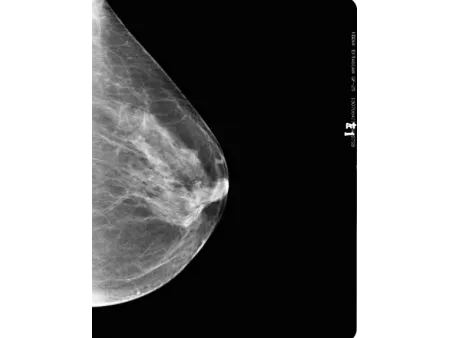

El detector plano CMOS, reconocido por su alta sensibilidad, permite obtener imágenes mamarias con gran nivel de definición. Este mamógrafo también incluye el software especializado Console, que utiliza algoritmos avanzados de posprocesamiento para mamografía, facilitando la visualización de estructuras finas y mejorando la precisión en la interpretación clínica. Con una capacidad de resolución de 60 líneas por centímetro, es capaz de detectar microcalcificaciones tan pequeñas como 0.1 mm, lo que refuerza su utilidad en programas de detección precoz de cáncer de mama y en evaluaciones clínicas más específicas.